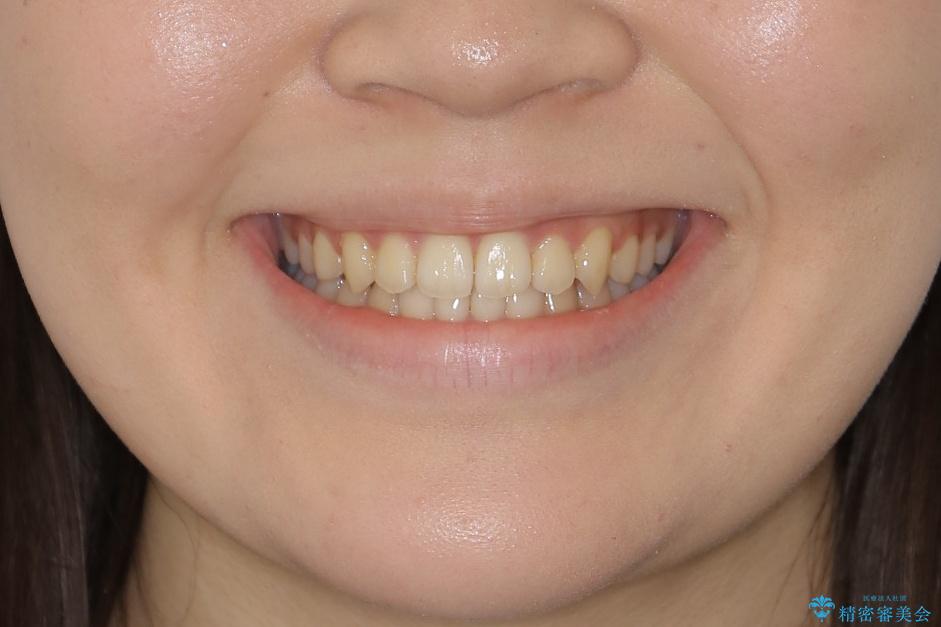

- 上の前歯のすきっ歯と下の前歯のガタつきを主訴にご来院されました。

噛み合わせの改善も同時に進めつつ、主訴の部分も効率的に治していくためマウスピース装置でゴムかけを行いながら治療を進めていきました。

正中離開(すきっ歯)

真ん中の歯が左右に開いてしまい隙間ができてしまう状態を「正中離開」といい、俗にすきっ歯と呼ばれています。

隙間を埋めていく方向に歯を移動させることで改善していくケースが多く、比較的治りやすい不正咬合のひとつとされています。

しかしながら、歯が捻じれていたり、噛み合う歯との位置関係によっては治療が難しくなる場合があります。